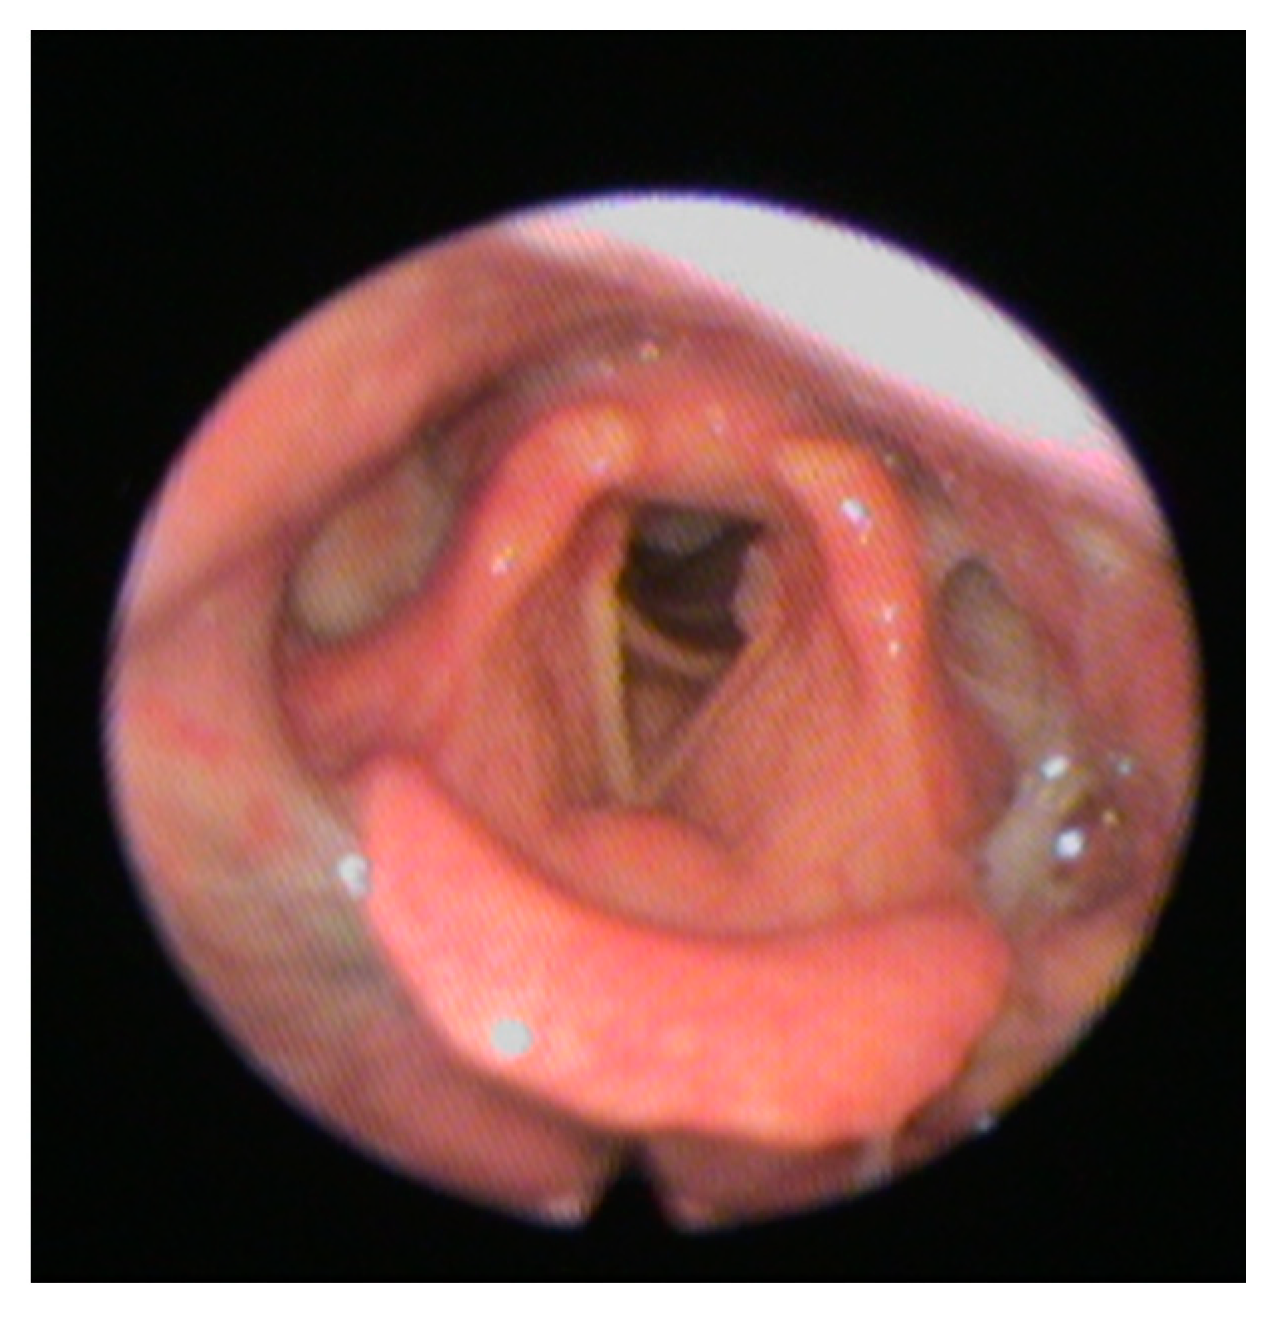

- Langmore, S.E.; Schatz, K.; Olsen, N. Fiberoptic endoscopic examination of swallowing safety: A new procedure. Dysphagia 1988, 2, 216–219. [Google Scholar] [CrossRef]

- Checklin, M.; Dahl, T.; Tomolo, G. Feasibility and Safety of Fiberoptic Endoscopic Evaluation of Swallowing in People with Disorder of Consciousness: A Systematic Review. Dysphagia 2021, 1–10. [Google Scholar] [CrossRef] [PubMed]